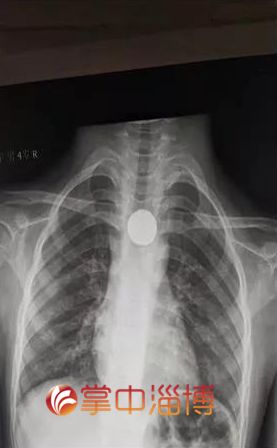

近日,一名10岁孩子不慎将一枚一元硬币吞下,因1元硬币直径较大,卡在孩子食管。

孩子出现了恶心、吞咽困难等表现,面部表情十分痛苦,所幸硬币及时取出,对孩子未造成严重的损伤。